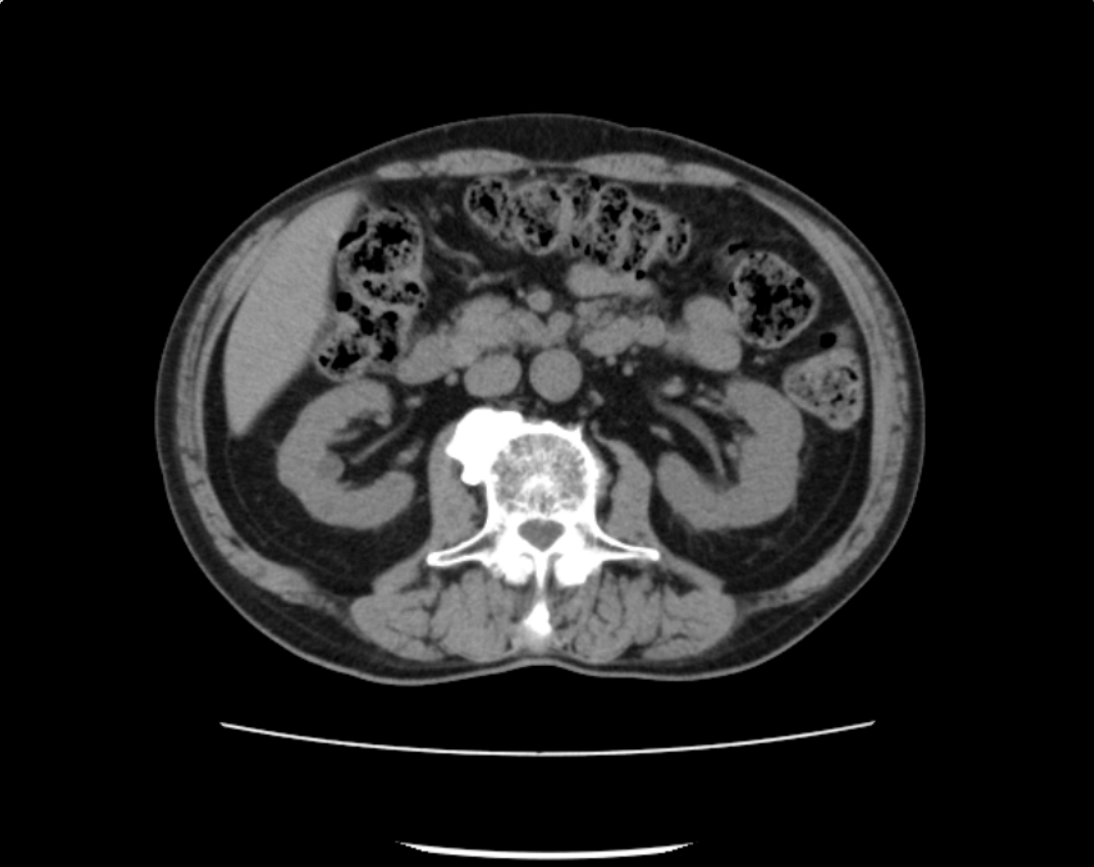

CT Aquilion lightningの導入

当院では新しいCTを導入いたしました。

高速マルチスライスでの撮影によって、従来のCT検査よりも短い時間で検査を受けることが出来ます。

撮影の際、体の部位に対して最適線量での撮影を自動調整できるため、被ばく低減が可能になりました。

新しいCTでは開口径を780㎜と広くすることによって狭い場所が苦手な方でも安心して検査を受けていただけます。